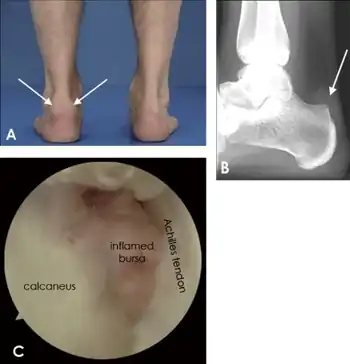

Retrocalcaneal bursitis

Retrocalcaneal bursitis is an inflammation of the bursa located between the calcaneus and the anterior surface of the Achilles tendon.[1] It commonly occurs in association with rheumatoid arthritis, spondyloarthropathies, gout, and trauma.

The pain is usually on the back of the heel and swelling appears on lateral or medial side of the tendon.